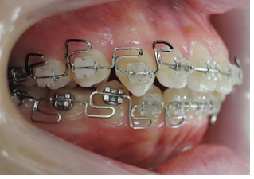

治療は上顎から矯正装置を装着していきます。

その後下顎の矯正装置を装着します。

この過程で歯並びが整いMEAW(マルチループ)を装着しやすくなります。

MEAW(マルチループ)を使用する事で上顎前突(出っ歯)や咬合高径(咬み合わせの高さ)の改善をしています。

☆治療途中

MEAW(マルチループ)を使用する事で上顎前突(出っ歯)や咬合高径(咬み合わせの高さ)を改善して2年6ヶ月で非抜歯での治療で綺麗な歯並びになりました。

当院の治療では、上顎から矯正装置を装着していきます。

MEAW(マルチループ)を使用する事で、上顎前突(出っ歯)や咬合高径(咬み合わせの高さ)の改善をしています。

MEAW(マルチループ)を使用する事で、上顎前突(出っ歯)や咬合高径(咬み合わせの高さ)を改善して2年6ヶ月で非抜歯での治療で綺麗な歯並びになりました。